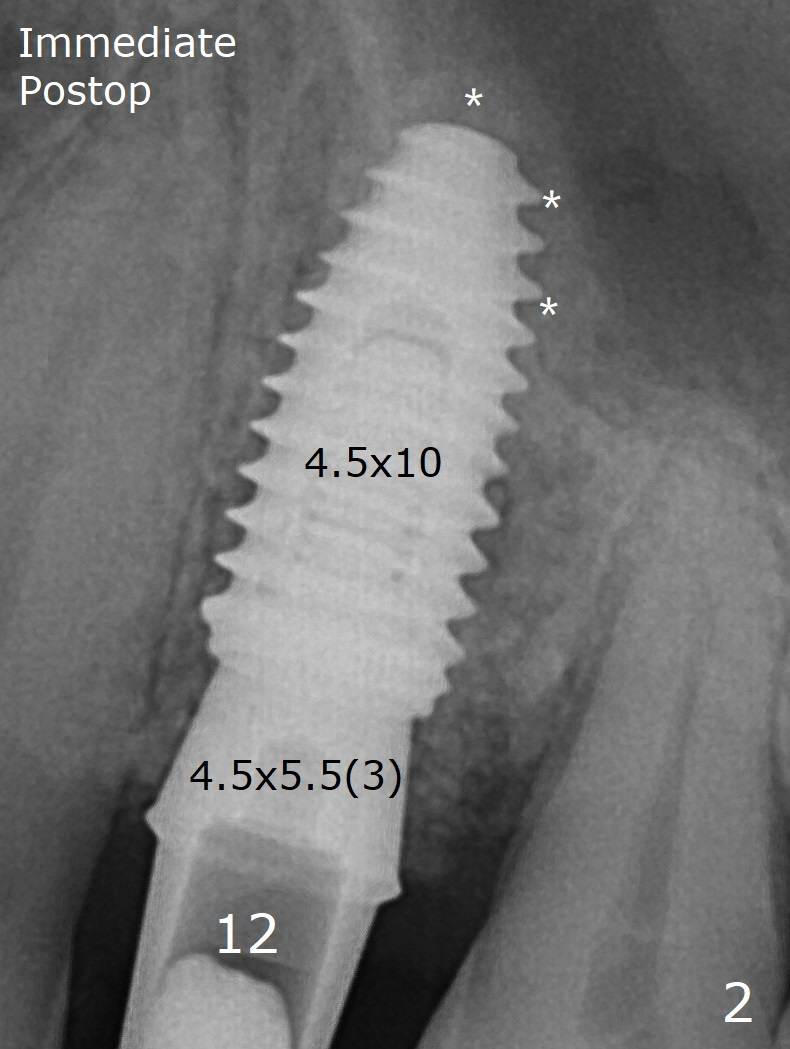

Sinus lift with Regular Drills Last Next